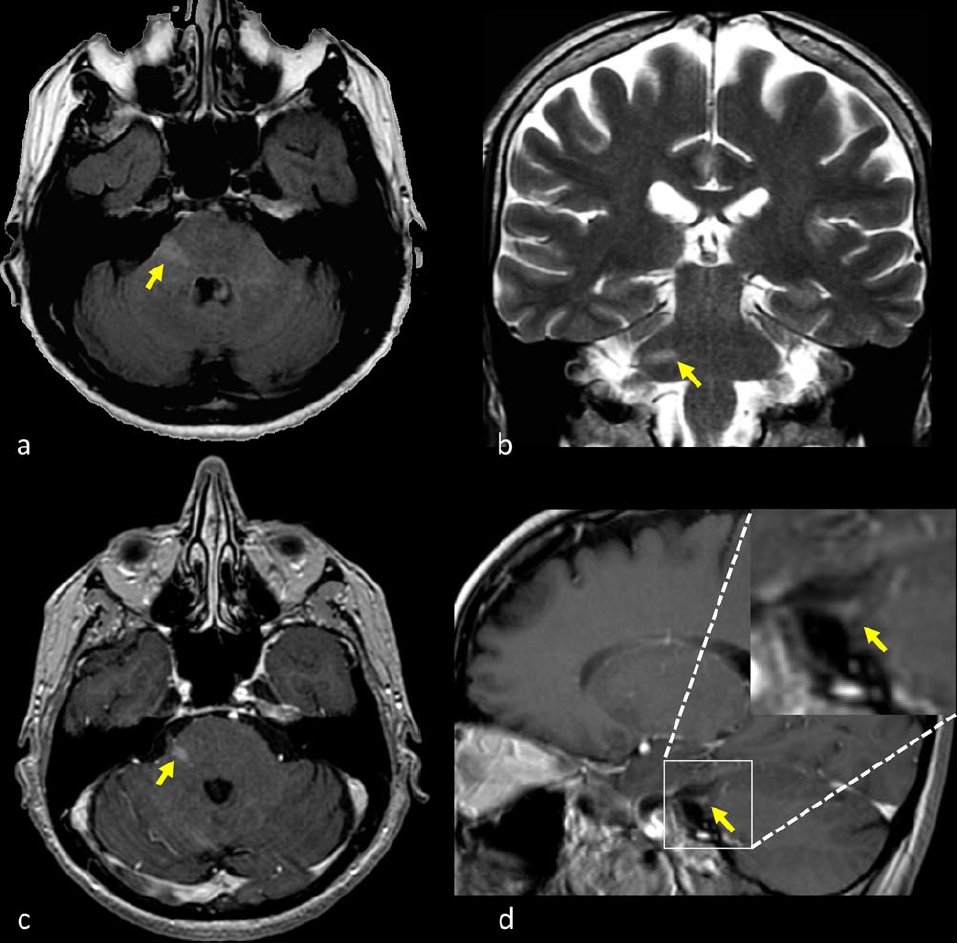

All’inizio dell’anno in Montallegro è entrata in funzione la nuova risonanza magnetica che, aggiungendosi alla strumentazione acquisita negli scorsi mesi […]